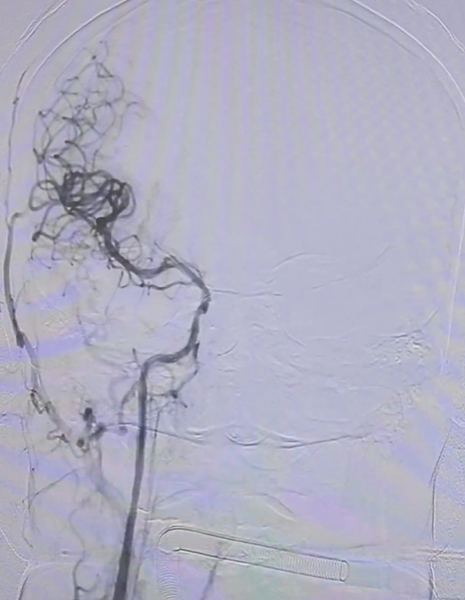

(3) 精准支架植入:为血管架起"长期保护桥",复查造影示:支架贴壁良好,管腔通畅,无残余狭窄。

从穿刺到血管完全再通,团队以最少的器械交换次数完成了这一急救操作,最大程度降低了手术相关并发症风险。